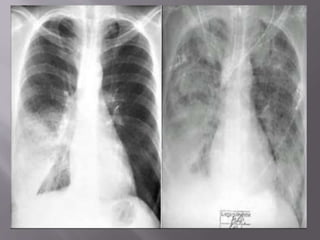

๏‚จ a clinical syndrome of severe dyspnea of rapid

onset, hypoxemia, and diffuse pulmonary infiltrates

leading to respiratory failure.